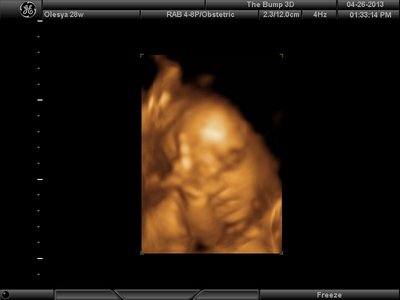

А я вчера на 3Д УЗИ ходила. Моя звезда закрывалась в еми 4мя конечностями. Просто пополам сложилась и спала себе сладко. УЗИстка провела со мной час, кое-как расшевелили маленькую, но ручка была постоянно на мордашке и засыпала она почти сразу снова. Я и на мяче прыгала и живот трясла. В конце более-менее фото вышли, но качество меня не порадовало. Возможно фри оф чардж еще раз переделают. Со средней фотки были отличного качества, а эти сплошное разочарование. Вот тут что-то более-менее еще. Главное пальчик оттопырила так смешно, мол минуточку. Вообще немного жутковатые фотки..хаха

| Вложения: |

image.jpg [ 47.86 КБ | Просмотров: 1458 ]